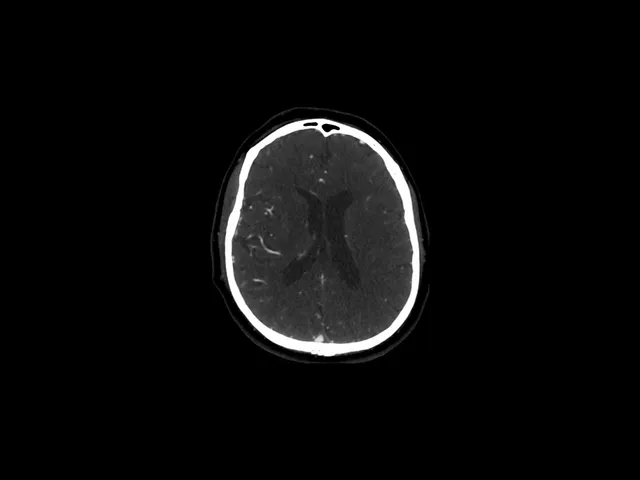

CT Angiography in Cerebrovascular Diseases

This comprehensive CT Angiography (CTA) training course offers in-depth insights into cerebrovascular imaging, including Ischemia, Hemorrhage, and Venous Pathology.

Day 2 explores haemorrhage, including CT bleed patterns and vascular anomalies like aneurysms and AV malformations.

• Interpret Ischaemia and Occlusion Patterns: Assess collateral circulation and parenchymal changes in ischaemic stroke, and recognize occlusion patterns in the major cerebral arteries (MCA/ACA, carotid, posterior circulation).

• Identify and Characterize Haemorrhage and Vascular Abnormalities: Recognize CT patterns of intracranial haemorrhages, aneurysms, arteriovenous malformations, and dissecting aneurysms, and understand their clinical significance.